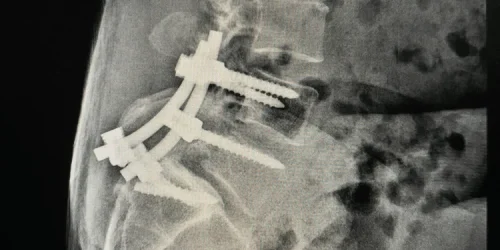

Definitive Treatment: Targeted Endoscopic Care

Deuk Laser Disc Repair® for Traumatic Disc Injuries

For traumatic disc injuries causing chronic neck pain, the Deuk Laser Disc Repair® provides targeted treatment that addresses the structural problem:

- Removes Inflammatory Tissue: Using laser energy and specialized instruments, I remove the inflammatory tissue from the posterior annular tear

- Debrids the Tear: Careful debridement of the damaged area eliminates the pain source

- Allows Natural Healing: Once inflammatory tissue is removed, the tear can heal naturally over 9-12 months

- Prevents Degeneration: Early treatment stops the progression from acute injury to chronic degenerative disc disease

- Preserves Motion: Unlike fusion, the procedure maintains your neck’s natural mobility

Procedure Details and Recovery

- Minimal Access: 4mm incision using endoscopic technique

- Duration: Approximately 20 minutes per disc

- Recovery: Patients walk within an hour after the procedure

- Return to Activities: Most patients return to normal activities within days to weeks